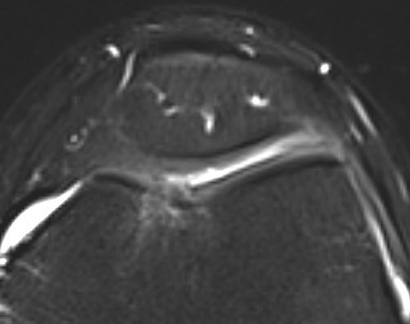

MRI

Microfracture of trochlea chondral defect

AMIC procedure of a full thickness patella lesion